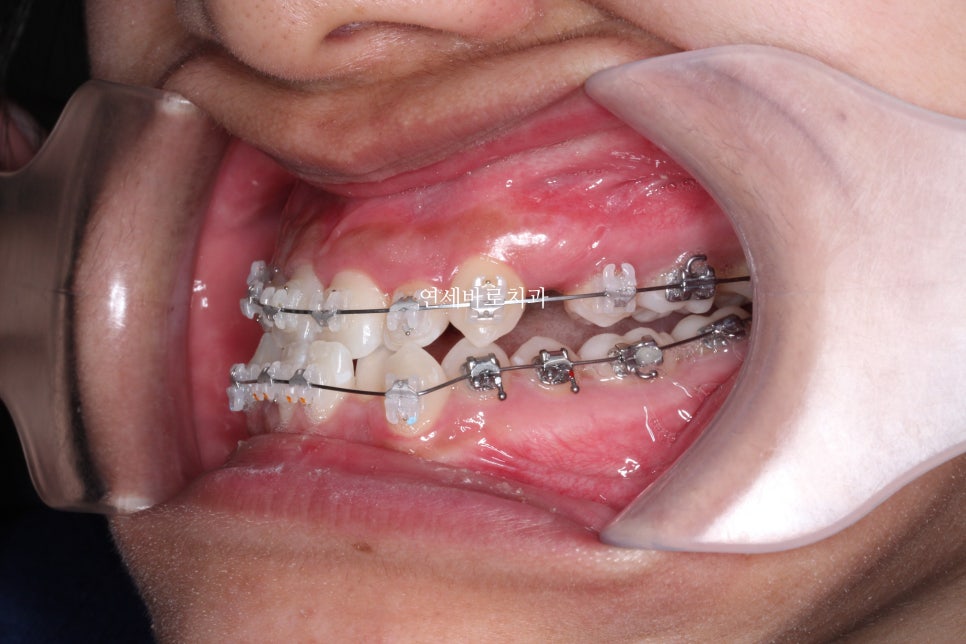

수술 직후의 위아래 모습입니다.

양악수술은 턱이 뒤로(후방) 들어가는 것 뿐만 아니라,

하안모(코아래부분)의 얼굴 길이가 줄어드는 것이 큰 장점이라고 생각합니다.

교정으로 어느정도는 시도할 수 있지만,

치아교정 단독과는 비교할 수 없을 만큼 양악수술로 해결할 수 있는 양은 큽니다.